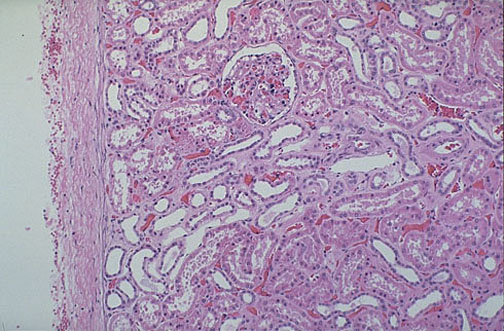

The normal kidney at low power has a thin connective tissue capsule at the left with underlying renal cortex which here contains a glomerulus and surrounding tubules with cuboidal epithelium.